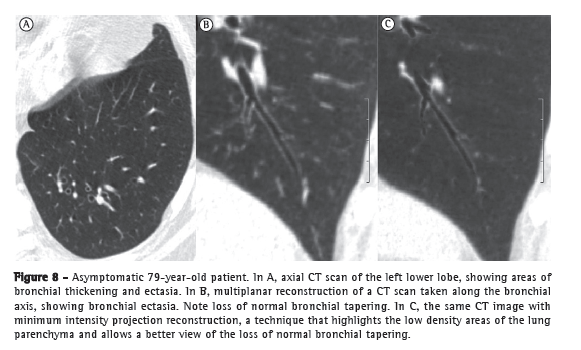

A CT scan of the lung parenchyma shows findings that are quite common in the elderly, and it is speculated that these findings are related to collagen changes. These findings are laminar atelectasis, mostly posterior and basal, located in the dependent regions of the lungs (Figure 5); subpleural linear thickening (Figure 6); areas of air trapping (Figure 7); bronchial thickening and ectasia (Figure 8); and lung cysts.(41,50-53)